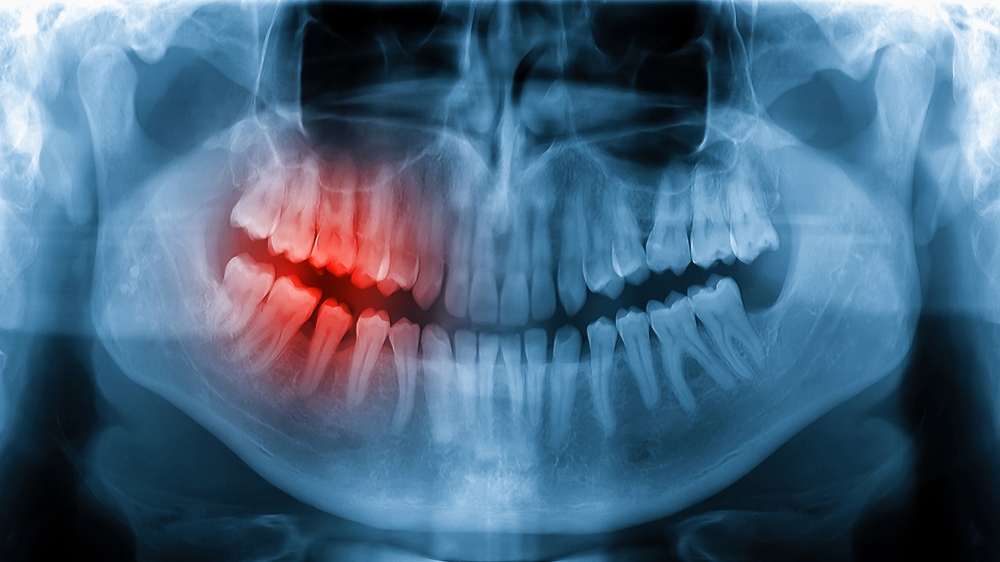

Når nerven i en tann er betent eller død, kan rotfylling fjerne årsaken til smerten og bevare tannen. Hos Tannlegebislett utfører vi skånsom og presis rotbehandling med moderne utstyr.

Ubehandlet betennelse i tannens nerve kan gi sterke smerter, hevelse og infeksjon som sprer seg.

Vi starter med røntgen og en nøye undersøkelse. Etter en solid lokal bedøvelse, isolerer vi omådet for å forebygge bakteriell foreurensing.

Deretter rengjør vi rotkanalene, desinfiserer dem og fyller dem tett igjen med plastikmateriell. Rotfyllingsterapi er en innvendig rotkanalbehandling og tannen må etterpå bygges opp med fyllingsmaterieller eller en krone for varig styrke.